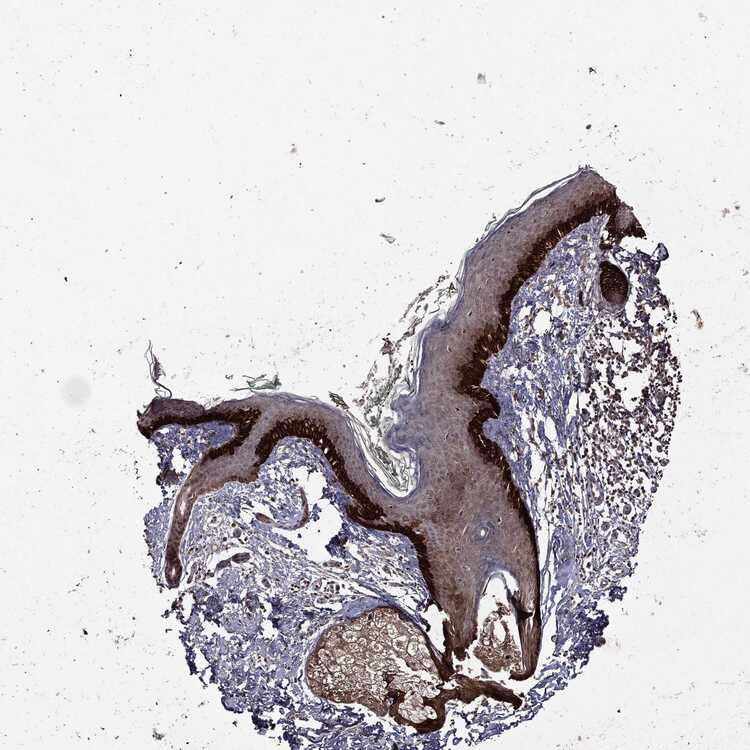

SKIN 1 - Antibody stainingi

Antibody staining in the annotated cell types in the current human tissue is reported as not detected, low, medium, or high, based on conventional immunohistochemistry profiling in selected tissues. This score is based on the combination of the staining intensity and fraction of stained cells.

Each image is clickable and will lead to virtual microscopy that enables deeper exploration of all samples and also displays staining intensity scores, fraction scores and subcellular localization as well as patient and tissue information for each sample.

Antibody CAB069425Antibody CAB080053Antibody CAB080065Antibody CAB080070Antibody CAB080081Antibody CAB080095Antibody CAB080097

Langerhans Not detectedNot detectedMediumNot detectedNot detectedNot detectedNot detected

Fibroblasts Not detectedNot detectedMediumMediumNot detectedMediumNot detected

Keratinocytes MediumMediumLowNot detectedNot detectedLowNot detected

Melanocytes Not detectedHighNot detectedMediumNot detectedMediumMedium